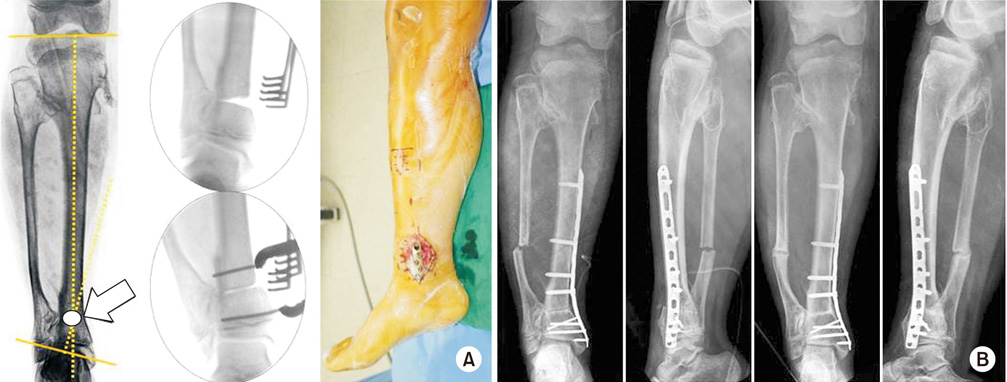

Fig. 3

(A) After intramedullary nailing of the proximal tibial shaft fracture, non-union with anterior angulation was confirmed. The center of rotation of angulation was identified (arrow). (B) The angulation was corrected by exchanging the nailing with a blocking screw at the proximal fragment. Six months later, the bony alignment and union was achieved.

jkfs-30-219-g003.jpg

Fig. 4

(A) In a 13-year-old male with valgus deformity due to osteochondroma, center of rotation of angulation was located at the distal tibia (arrow). We performed a medial close wedge osteotomy and restored the alignment by compressing the gap of osteotomy. The osteotomy site was fixed with minimally invasive plate osteosynthesis. (B) The anatomical alignment was recovered after operation. Six months later, bony union was completed.

Fig. 3 (A) After intramedullary nailing of the proximal tibial shaft fracture, non-union with anterior angulation was confirmed. The center of rotation of angulation was identified (arrow). (B) The angulation was corrected by exchanging the nailing with a blocking screw at the proximal fragment. Six months later, the bony alignment and union was achieved.

Fig. 4 (A) In a 13-year-old male with valgus deformity due to osteochondroma, center of rotation of angulation was located at the distal tibia (arrow). We performed a medial close wedge osteotomy and restored the alignment by compressing the gap of osteotomy. The osteotomy site was fixed with minimally invasive plate osteosynthesis. (B) The anatomical alignment was recovered after operation. Six months later, bony union was completed.